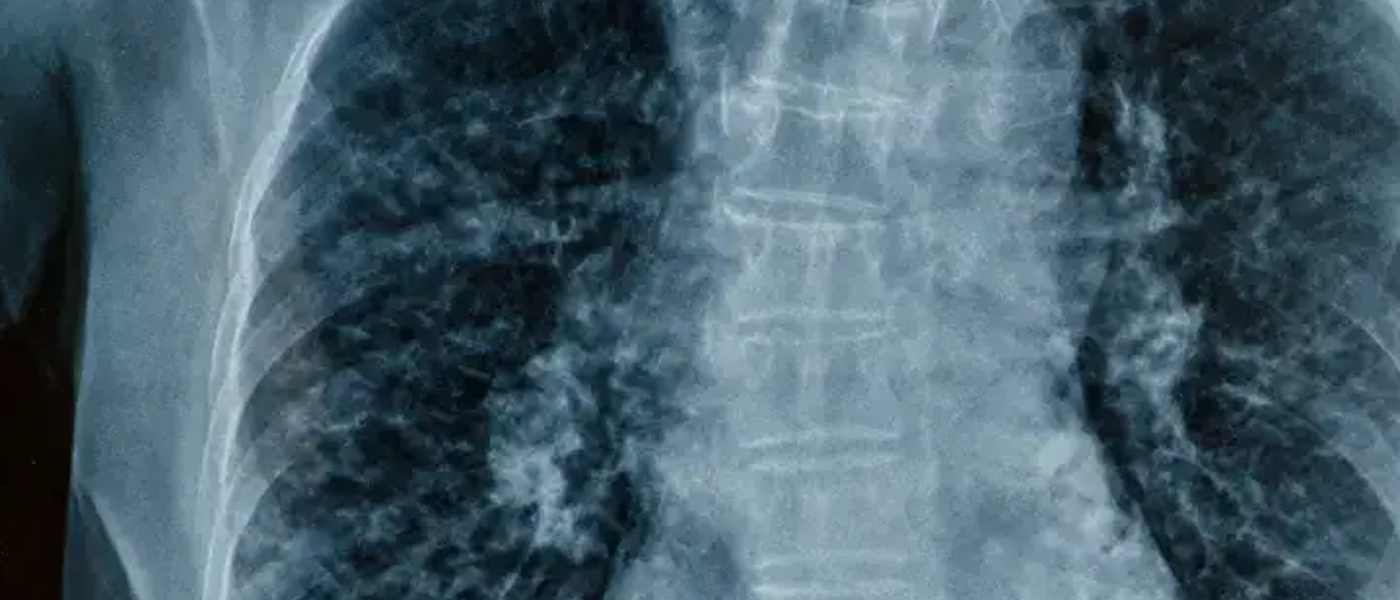

Mesothelioma is a rare and aggressive form of cancer that develops in the mesothelium, the protective lining that covers many of the body's internal organs. This devastating disease is almost exclusively caused by exposure to asbestos, a once widely used mineral known for its heat-resistant properties.

1. Pleural Mesothelioma: The most common form, affecting the lining of the lungs (pleura). It accounts for about 90% of all mesothelioma cases.

Diagnosis typically involves imaging tests (X-rays, CT scans), biopsies, and blood tests. A thorough medical history, including potential asbestos exposure, is crucial for accurate diagnosis.